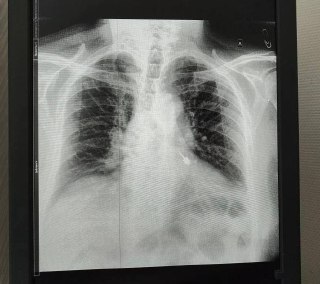

🤯Стоматологический бур провалился в бронхи мужчины во время лечения зубов в Подмосковье.

Он сразу почувствовал боль в груди и обратился в больницу.

👨‍⚕️Врачи провели с помощью эндоскопа извлекли инструмент, сейчас с пациентом всё в порядке.